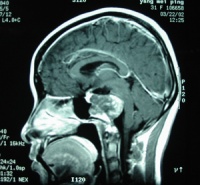

核磁共振成像(MRI)